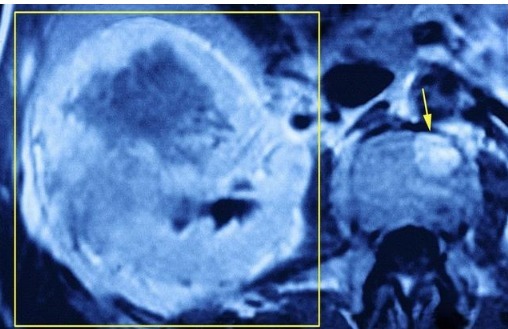

- 胶质瘤是脑内最常见的恶性肿瘤之一|胶质瘤能治好吗?复发后有必要再次手术吗?医生说了实话